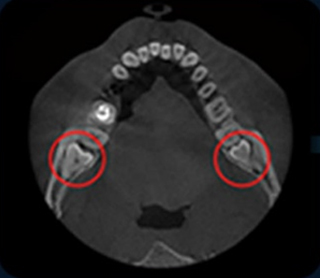

CT 촬영 정밀검진 -

3D 컴퓨터 모의시술 및